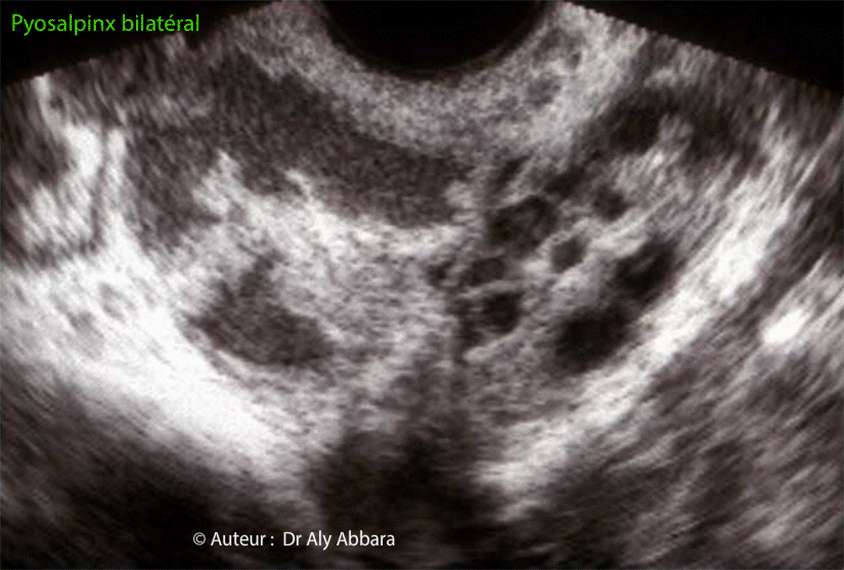

Image animée montrant un des aspects échographiques des trompes atteintes de salpingite aiguë bilatérale prédominant à droite avec la formation d'abcès intra-tubaire bilatéral (pyosalpinx). |

| Le diagnostic de salpingite aiguë a été confirmé suite à la réalisation d'une cœlioscopie exploratrice permettant la mise en évidence de la présence de deux trompes congestives, indurées, inflammatoires, enroulée et adhérant à la paroi pelvienne latérale homolatérale avec des extrémités distales obturées. La trompe droite et deux fois plus volumineuse que la trompe gauche, et chacune d'entre elle est le site d'une collection purulente occupant sa lumière tubaire (pyosalpinx). L'exploration de la région péri-hépatique montre la présence d'une péri-hépatite (ou syndrome de Fitz Hugh Curtis) se manifestant par la présence de nombreuses adhérences hépato-pariétales antérieures et hépato-diaphraqumatiques en cordes de violon. L'exploration bactériologique montre qu'il s'agit d'une infection génitale haute à chlamydia trachomatis. A comparer avec une salpingite sans pyosalpinx. |